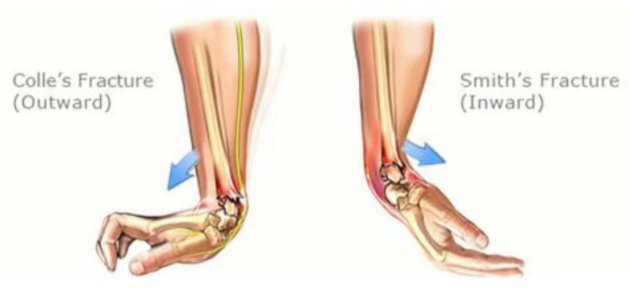

2.腕关节畸形,可像餐叉状、刺刀样;

累及关节面的粉碎性骨折、开放性骨折、保守治疗效果欠佳者就需要进行手术治疗。就是通过做手术在直视下把骨头断的地方对好,然后用钢板、螺钉或者克氏针固定住,维持骨断端稳定不移位,待骨断端长在一起就痊愈了。